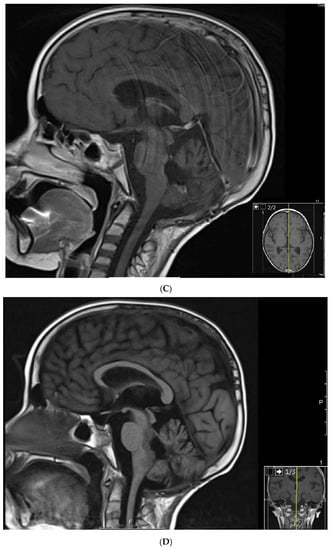

Figure 2.

Patient 2: MRI shows confluent encephalomalacia gliosis in the left temporal and occipital lobes. There was no evidence of mass or pathologic enhancement 8 years from diagnosis and 4 years off therapy.